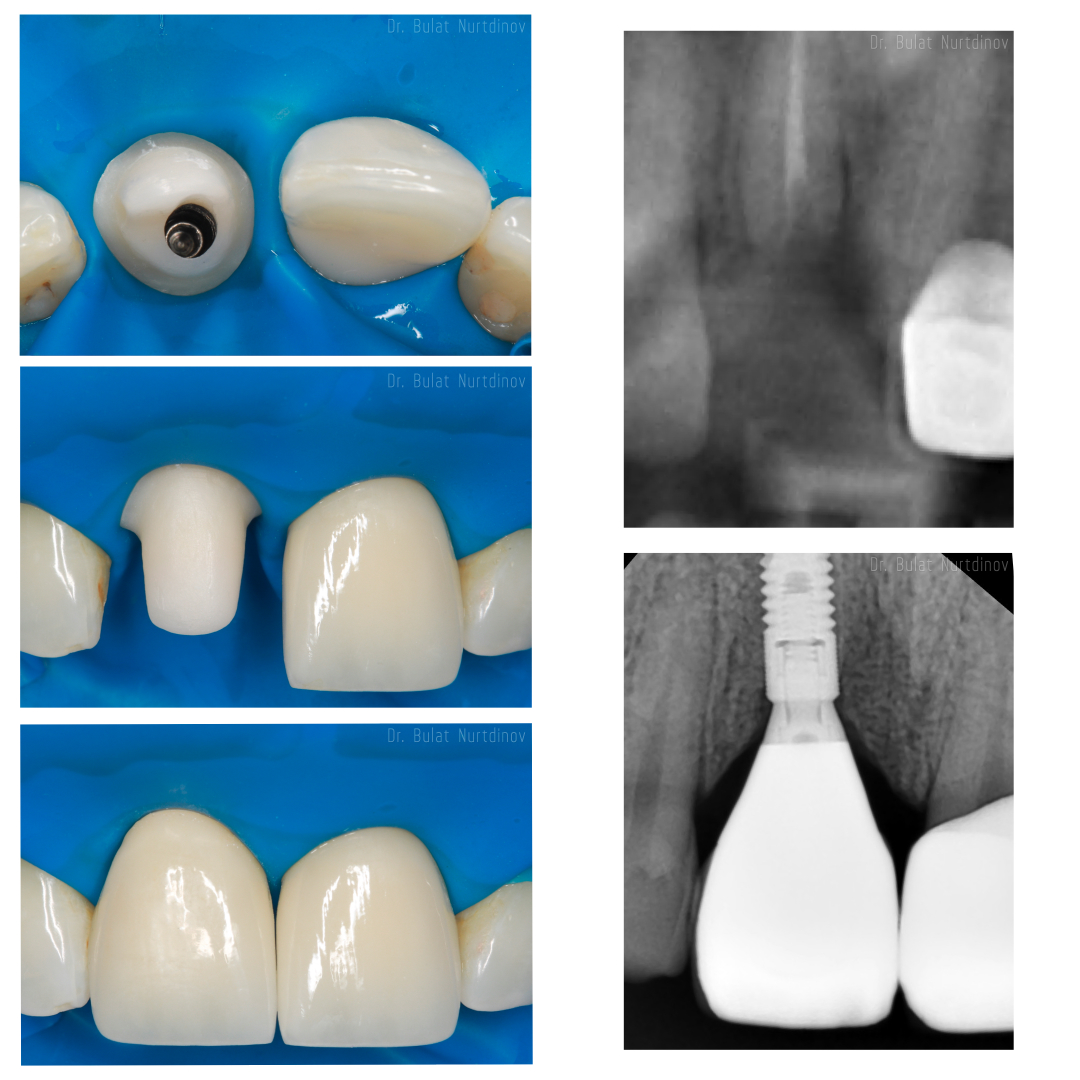

Зубной имплант - это неживой предмет, соединённый с живой тканью и выполняющий функцию замещения отсутствующего зуба. Имплант, как и зуб, имеет два основных отдела: внутрикостную и коронковую (внешнюю) части. Первая входит в кость, служит опорой для будущего зуба и, таким образом, имитирует корень. Во внешнюю часть, которая располагается над десной, устанавливается коронка, имитирующая непосредственно зуб.

В клинике «Стомус» используют традиционную имплантацию корневидными имплантатами -и применяют такие запатентованные поверхности, как SLA, OsseoSpeed.